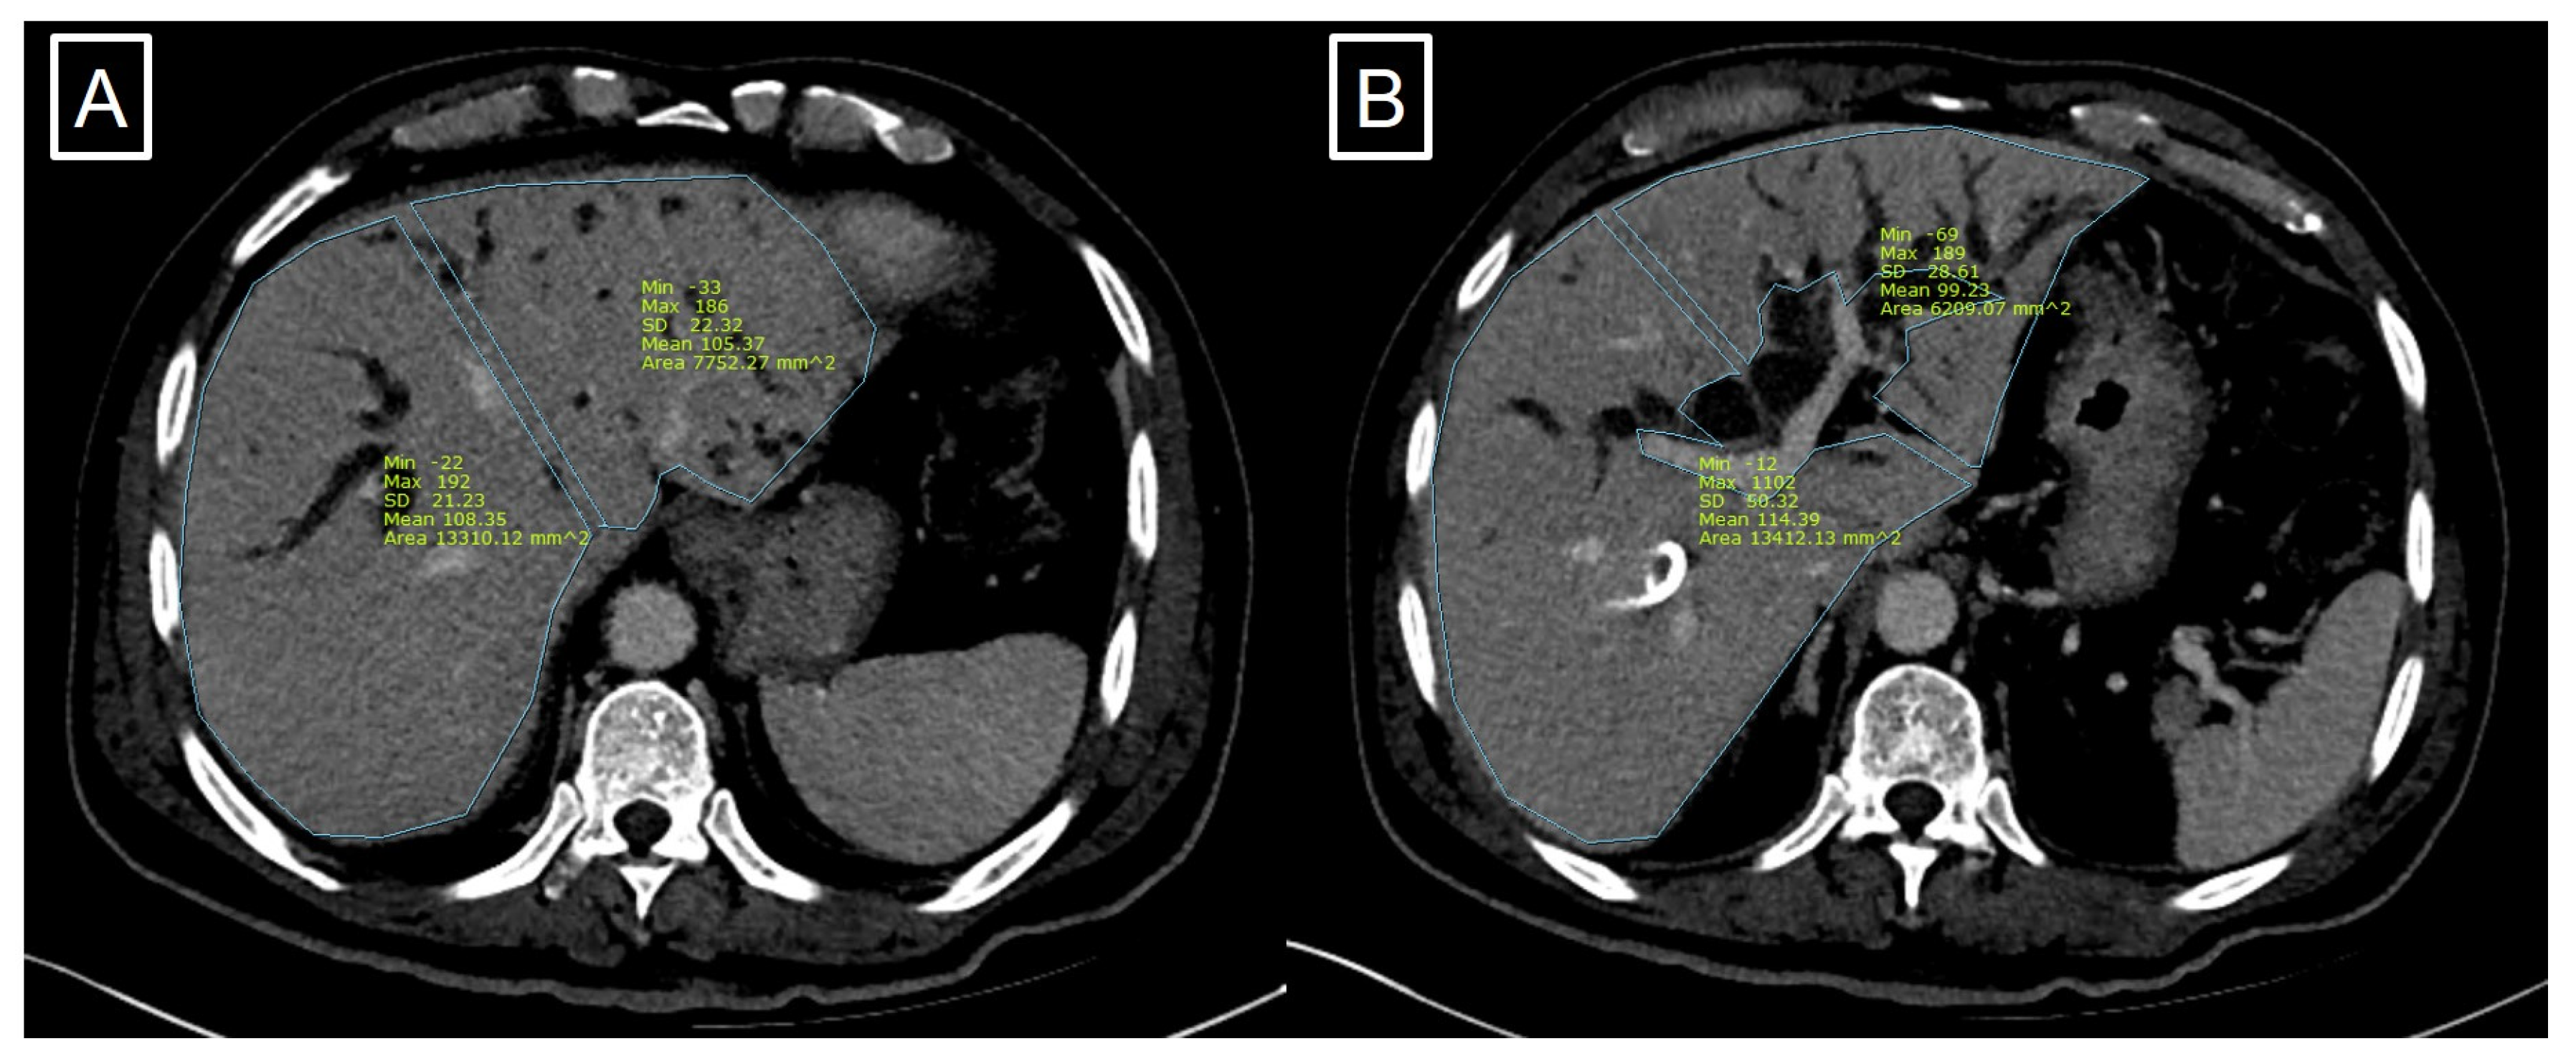

2.3. CT Volumetry Measurement

The most recent CT or MRI images derived prior to the operation were used for the CT volumetry. The margin of the left and right hepatic lobes was traced manually along Cantlie’s line, which divides the functional left and right hemi-livers [17], with consideration of the resection margins lateral to the middle hepatic vein and anatomical variations as depicted in Figure 1. The total volume of each hemi-liver was calculated by the addition of the area of hepatic parenchyma from each slice multiplied by the slice thickness. When we obtained the volumetric data of the left and right hemi-livers, we included the middle hepatic vein to the remnant left liver for right hemi-hepatectomy, and excluded the middle hepatic vein for extended right hemi-hepatectomy (Figure 2).

Figure 1. Virtual resection line is located on the right side of Middle hepatic vein (A). Virtual resection line on gall bladder level (B).

Figure 2. Virtual resection line is located on the left side of Middle hepatic vein (A). Virtual resection line on portal bifurcation level (B).